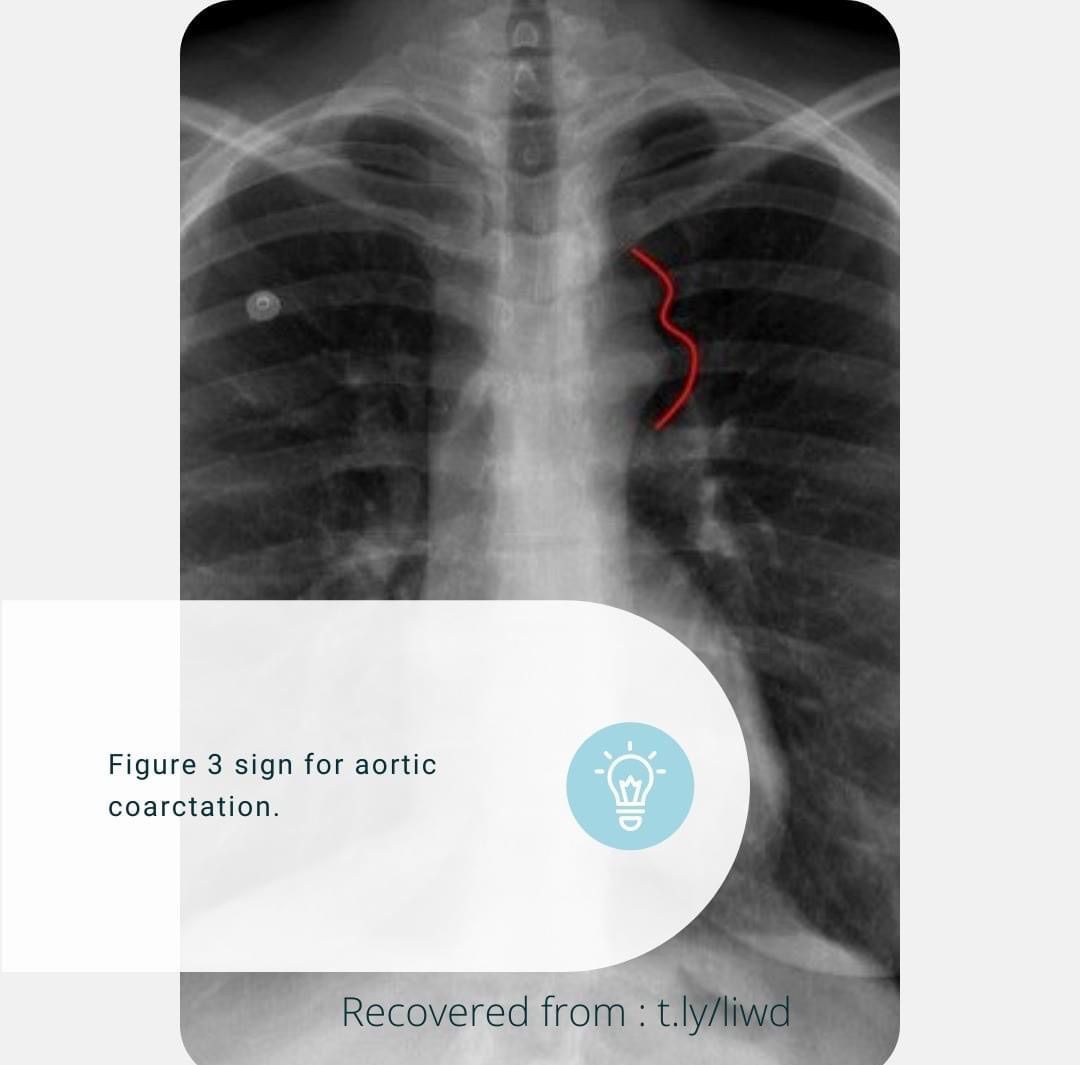

Aortic Coarctation

Cardiology

Internalmedicine

Coarctationofaorta